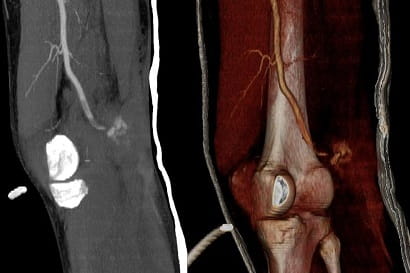

Born from innovation, interventional radiology (IR) works from the inside out, delivering minimally invasive procedures that allow patients to return to their lives as quickly as possible. At just over 50 years old, interventional radiology is a pioneer among medical specialties, providing image-guided procedures that target disease and enable minimally disruptive treatments.